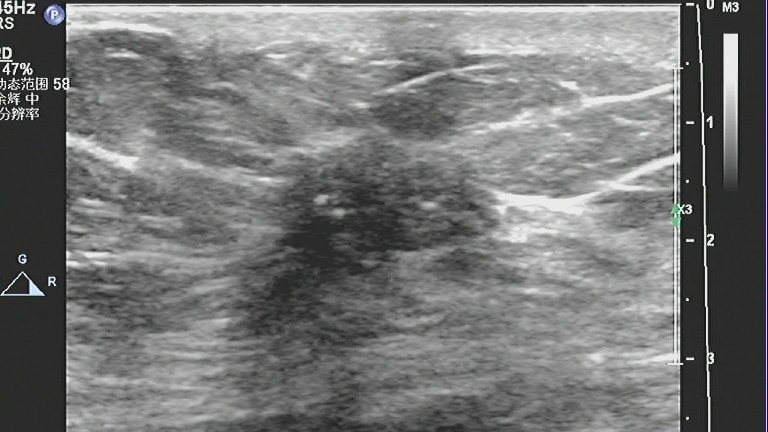

1、肿块多呈不均质的低回声,没有包膜,后方回声可衰减。